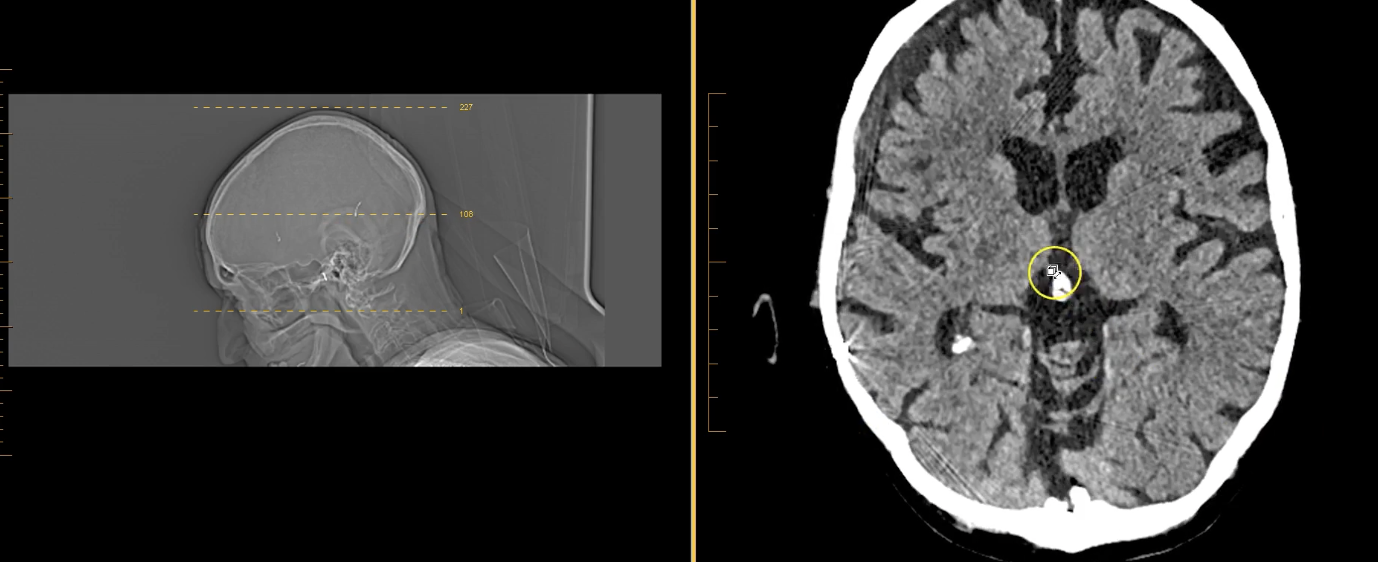

New cards

term image

lateral ventricles

thalamus